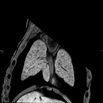

Caption: Mutant 2966-005-2 (E15.5) displays heterotaxy with mesocardia and left lung isomerism.

Caption: 2966-005-2 mutant exhibits mesocardia, hypoplastic right ventrical, perimembrnous and muscular VSDs, aberrant right subclavian artery forming incomplete vascular ring, left lung isomerism as seen by episcopic confocal microscopy.

Caption: Serial 2D episcopic confocal microscopy image stack in the coronal plane of 2966-005-2 (E15.5) reveals mesocardia, perimembranous ventricular septal defect (pmVSD), muscular ventricular septal defect (mVSD), aberrant right subclavian artery forming incomplete vascular ring, and left lung isomerism. Click thumbnail to play movie.